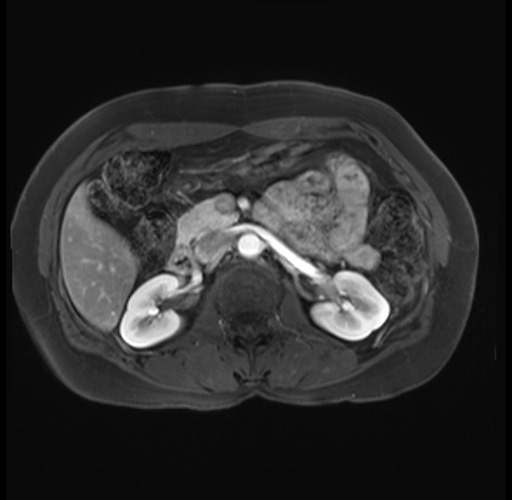

Imaging Analysis

Look through the patient's CT scan to identify any areas of concern for the necessary procedure.

Based on your CT findings, which issue(s) are present and would give reason for "planned slowing down moment(s)" in this case?